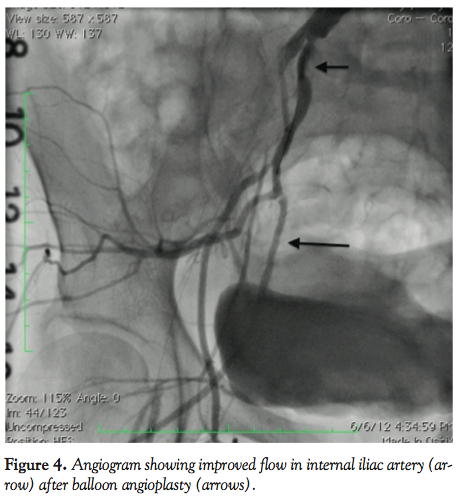

After left to right crossover with a 6 x 45 cm sheath, a Confianza wire (Abbott Vascular) was used to cross the CTO of EIA and a Fox SV 5.0 x 40 mm balloon (Abbott Vascular) was used for balloon angioplasty (BA) of the lesion. During and after BA, the patient experienced severe pain in the hip, right groin, and genital area. Repeat images showed compromised flow in the right IIA (Figure 3). There was no evidence for a perforation at the side of the pain, abdomen was soft and there was no tenderness or change in pain with deep palpation of the right groin. Then, a Prowater wire (Abbott Vascular) was advanced in the right internal iliac artery and a Fox SV 5.0 x 40 mm balloon (Abbott Vascular) was inflated at 4 atm with establishment of normal flow in the vessel with less than 20% residual and immediate

resolution of the pain (Figure 4). The EIA lesion was stented with Absolute pro 7.0 x 80 mm and 7.0 x 40 mm self-expanding stents (Abbott Vascular). Due to residual significant gradient in proximal edge of the first stent, a Protégé Everflex 8.0 x 20 mm self-expanding stent (ev3) was deployed across the IIA for full coverage of the ostial EIA and postdilated with a Fox SV 7.0 x 20 mm balloon (Abbott Vascular) with no residual stenosis or gradient (Figure 5). The flow in the IIA remained normal, but she experienced similar pain during postdilatation of the distal CIA/ostial EIA stent which self-resolved with deflation of the balloon. She was discharged home with no complications and did not have any